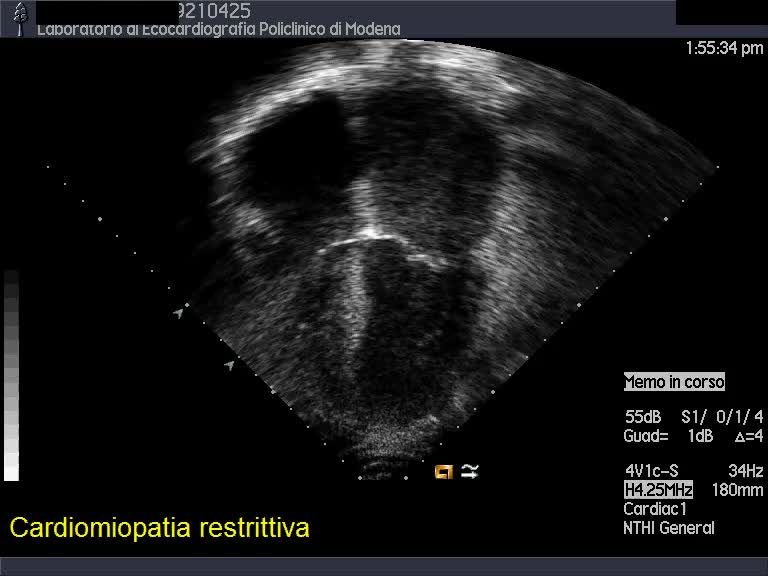

Titolo:

Cardiomiopatia restrittiva

Autore:

Andrea Barbieri